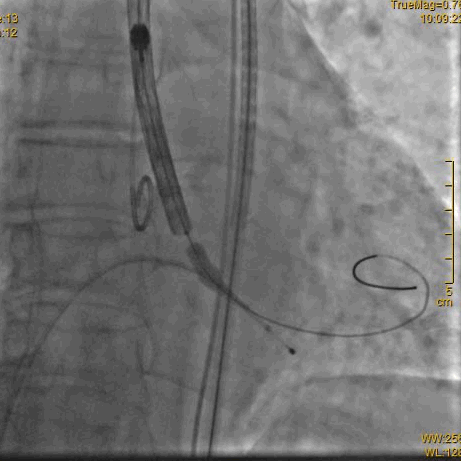

球囊预扩确认冠脉风险

瓣膜定位

瓣膜释放过程